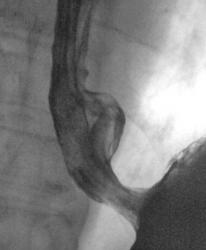

Пищевод.

Случай.

дивертикулы пищевода

Изображение  Изображение

Естественно есть признаки дивертикулита- в 1ю очередь слабо выражено, но 3-х слойность за счет наличия слизи.

"выпячивание" стенки пищевода, указанное над диафрагмой вероятнее всего ГПОД, склдки желудочного типа.